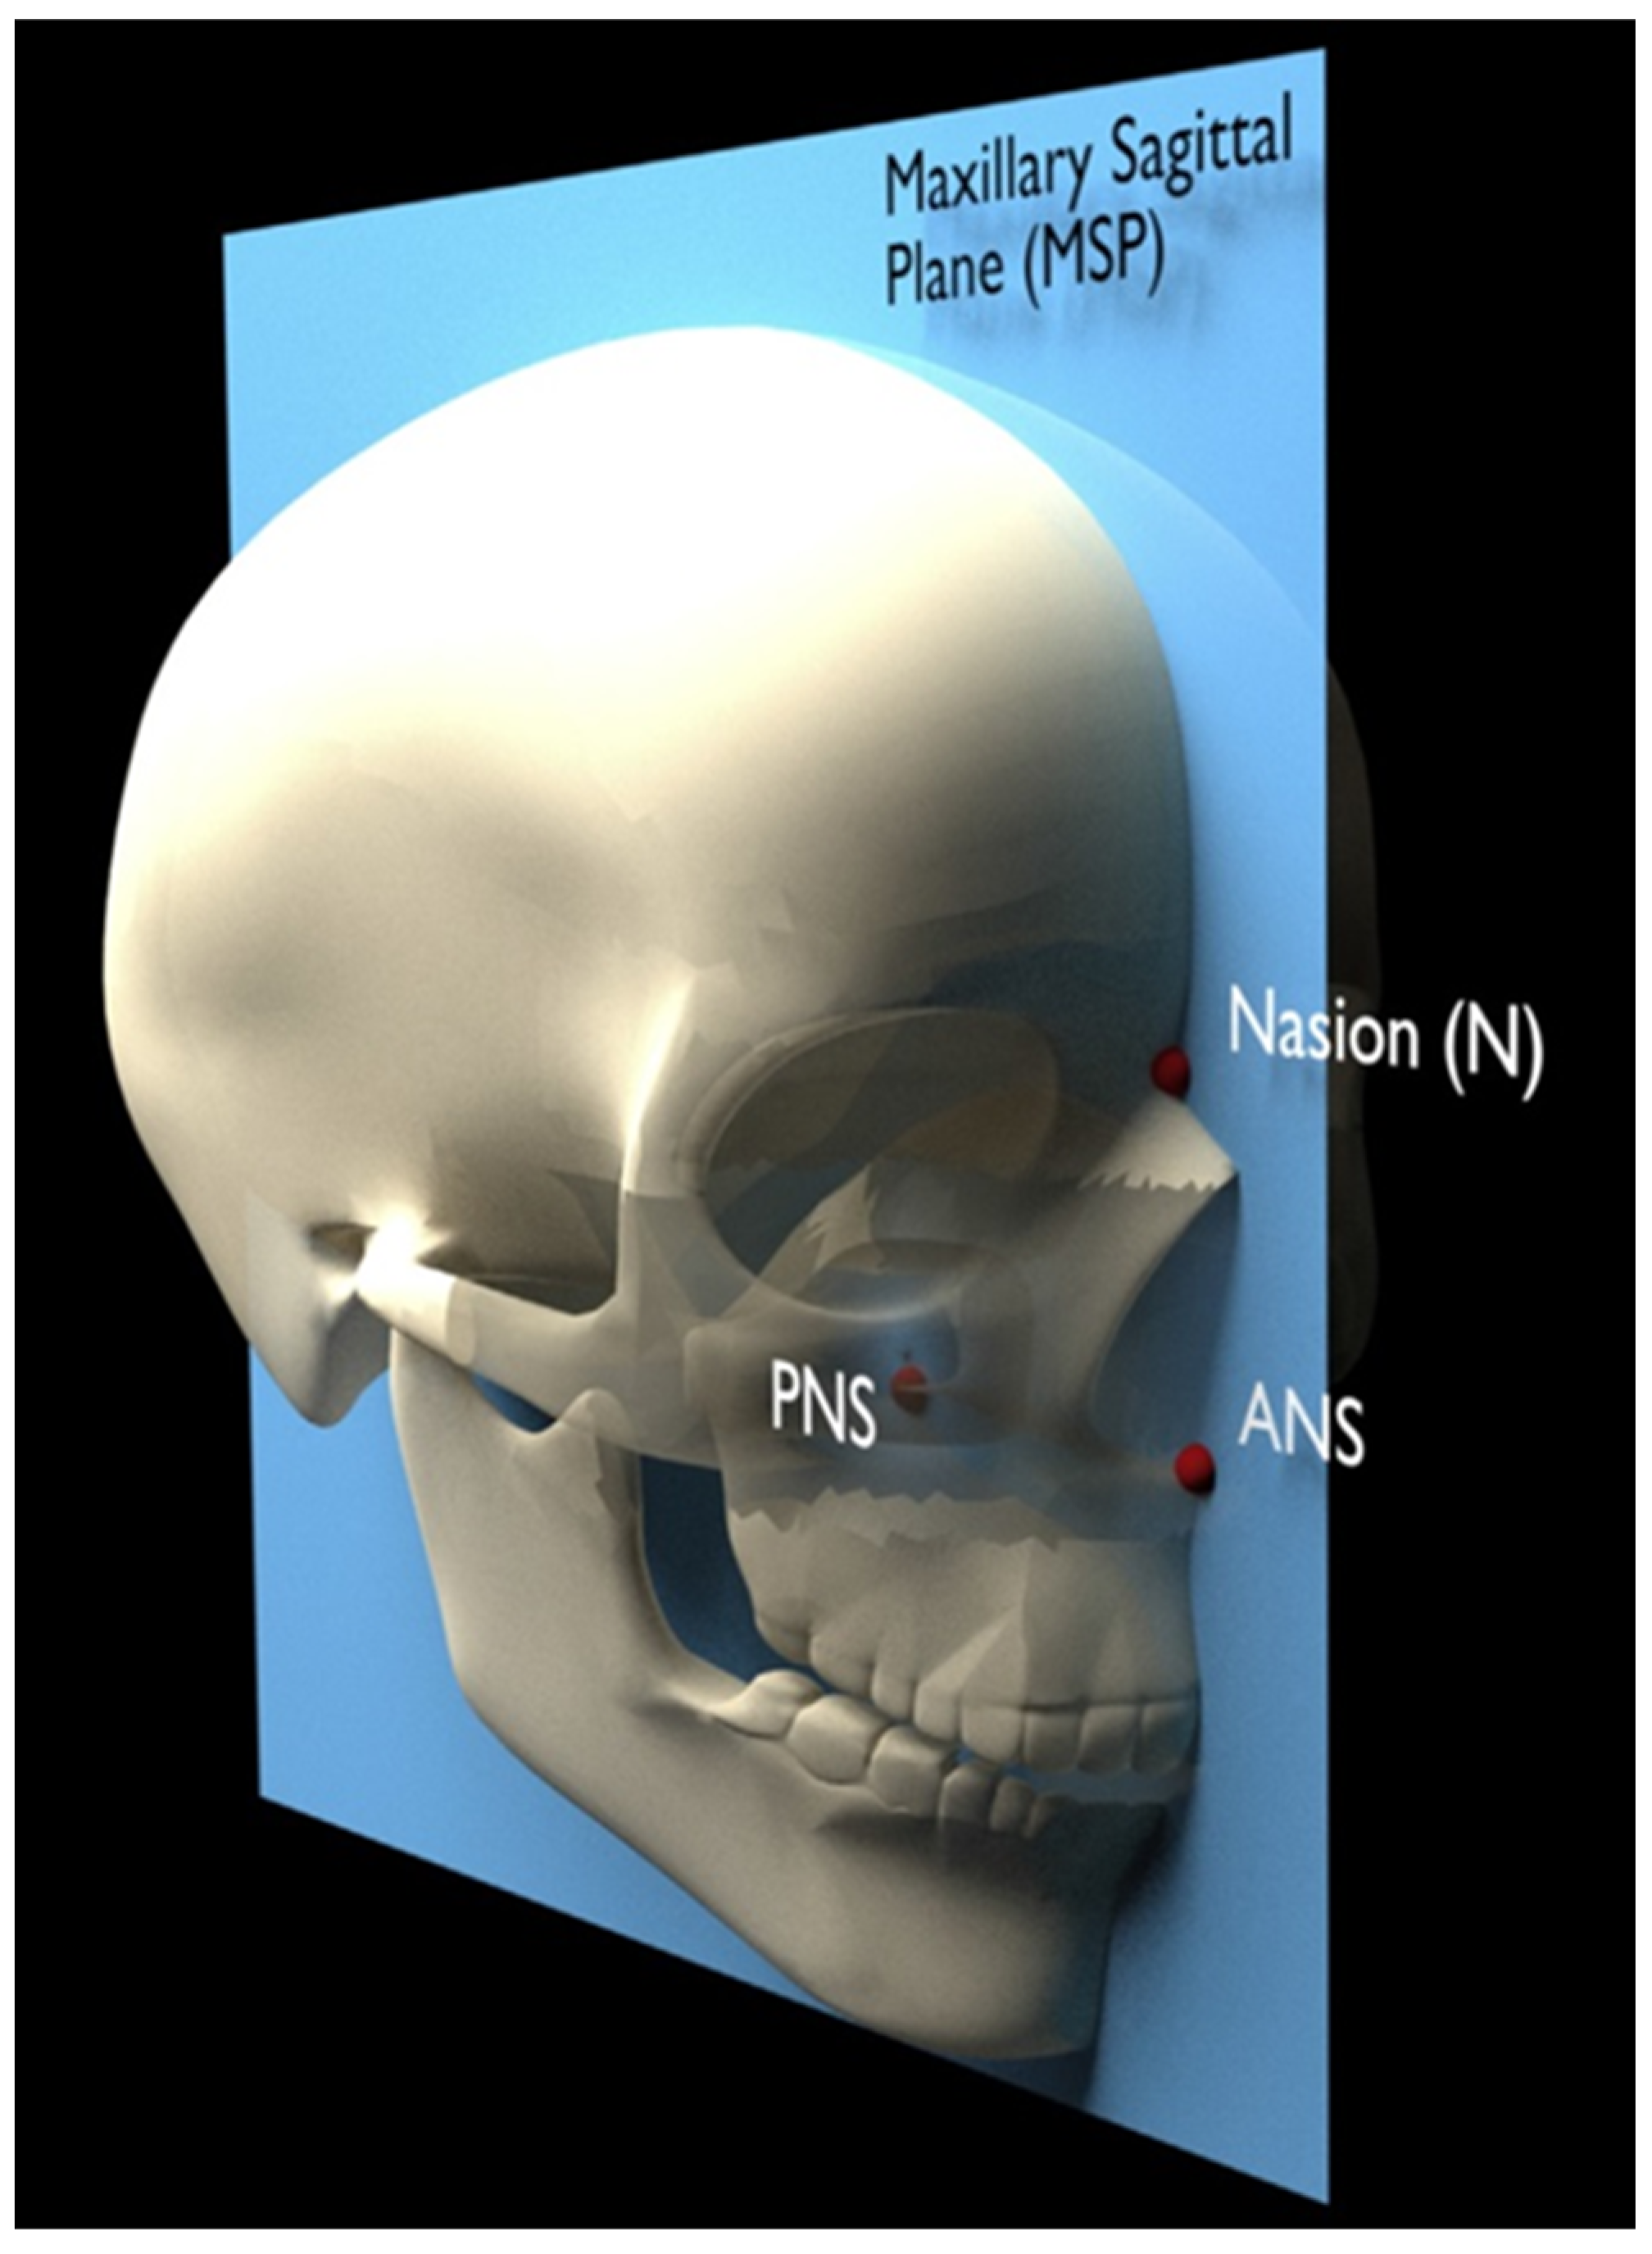

2.2. Evaluation Method